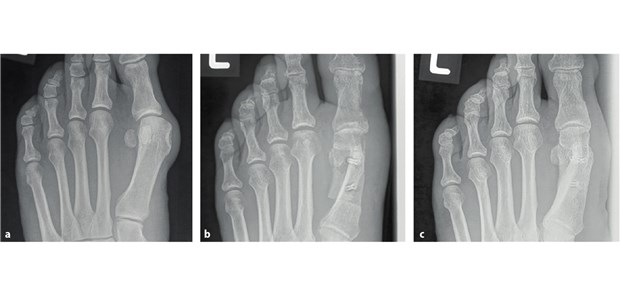

Abb. 1: Korrektur eines Hallux valgus: Die Röntgenbilder zeigen einen mit MgYREZr-Schrauben versorgten Hallux valgus am linken Fuß vor der Operation(a), mehrere Wochen(b) und ein Jahr nach der Operation(c)

© Syntellix AG